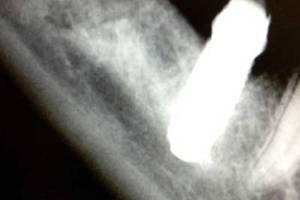

Dolor en la hemimandíbula derecha que le provocaba un implante demasiado cercano al nervio dentario inferior derecho y le provocaba una neuralgia del trigémino.

Explantación de la fijación dental 4.6 con sumo cuidado para no intruir más el implante ni perjudicar más al nervio.